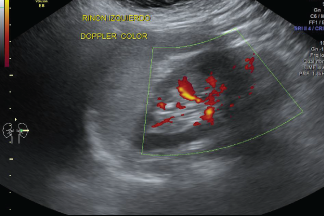

Debido a que las imágenes por ecografía se capturan en tiempo real, pueden mostrar la estructura y el movimiento de los órganos internos del cuerpo, como así también la sangre que fluye por los vasos sanguíneos.